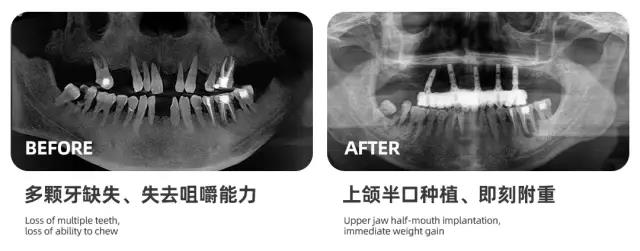

海德堡联合口腔UNIC种植中心崔雪冬主任从医学的角度告诉大家,当我们的牙齿脱落后,会形成一个空缺位置,长此以往,会造成周边牙齿逐渐松动乃至脱落。

而种植牙是目前最有效的解决缺牙问题的方式,海德堡联合口腔一直致力于通过德国标准的口腔诊疗服务帮助中老年人解决牙齿问题。

通过德国数字化口腔种植技术让更多牙齿缺失的人,在无痛舒适、快速精准的情况下种好牙齿。

在过去的一年,我们已经为天津上万缺牙市民进行了免费口腔检查,同时还为很多缺牙市民完成了种植牙修复,帮助他们彻底摆脱了缺牙吃不好饭、活动假牙不舒服的苦恼。